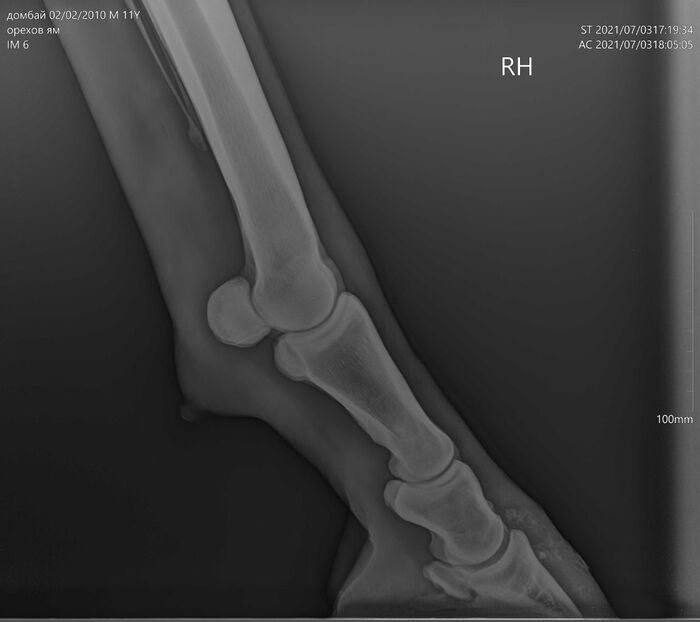

На этих x-ray снимках Домбай.

У него артроз (или артрит, я такой себе врач) пальчиков на руках.

Плюс косточка в копыте подходит очень близко к краю.